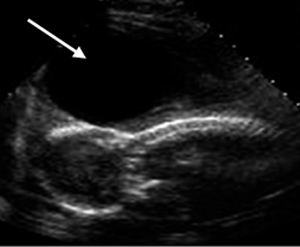

Β. Διαπαρεγκεφαλιδική απεικόνιση

1. Υπολογισμός της ηλικίας κύησης: Η διάμετρος (σε mm) της παρεγκεφαλίδας έως την 24η εβδ. αντιστοιχεί στην ηλικία της κύησης.(1,6,8)

2. Απεικόνιση θαλάμων, διαφανούς διαφράγματος, τρίτης κοιλίας, δρπάνου εγκεφάλου, παρεγκεφαλο- νωτιαίας δεξαμενής.

3. Μέτρηση παρεγκεφαλονωτιαίας δεξαμενής (φ.τ. <10mm): Αύξηση της διαμέτρου με συνοδό υποπλασία της παρεγκεφαλίδας σχετίζεται με υδροκεφαλία και σ. Dandy-Walker. Αντίθετα, εξαφάνιση της δεξαμενής συμβαίνει στη δισχιδή ράχη, όπου συνυπάρχει παραμόρφωση της παρεγκεφαλίδας (banana shape) και των μετωπιαίων οστών του κρανίου (lemon shape).(38)

4. Μέτρηση αυχενικής πτυχής: Συγκέντρωση λέμφου στο υποδόριο της ινιακής περιοχής που εμφανίζει θετική συσχέτιση έως και 70% με σ. Down εάν βρίσκεται (>6mm).(15,31,39)